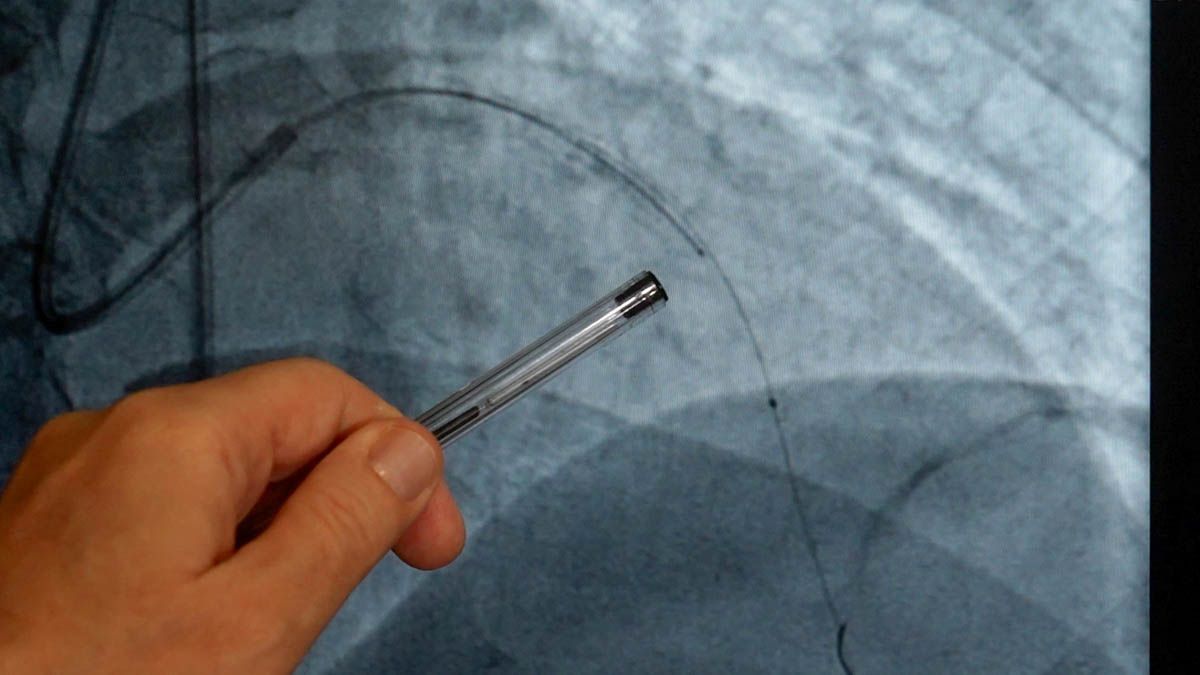

El IVUS representa un cambio significativo en la forma de estudiar las arterias. A diferencia de la angiografía tradicional, que muestra el paso del contraste, esta tecnología permite observar directamente el interior de la pared arterial.

“Estamos acostumbrados a ver las arterias mediante radiología, pero esto permite inspeccionar el interior, conocer la composición de la obstrucción y entender si hay calcio, colesterol o tejido fibroso”, explicó Moles.

El IVUS también permite verificar el resultado final: “Después de colocar el stent, podemos chequear que esté bien expandido y bien pegado a la pared. Esa información no la teníamos antes”.